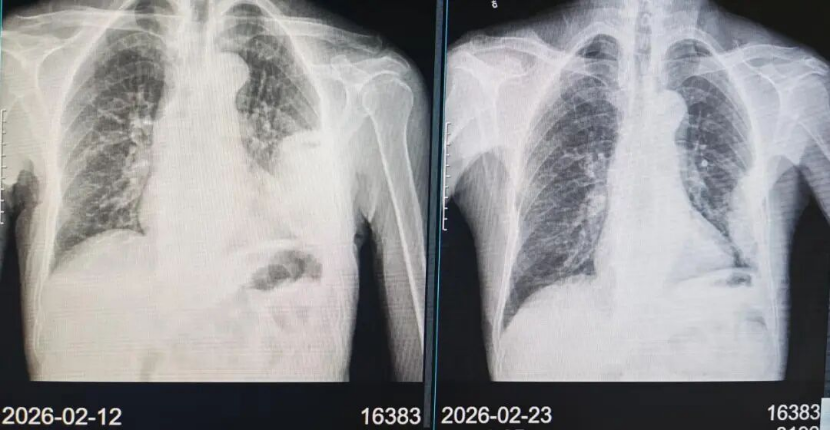

治疗:患者同意参加由中日友好医院牵头,上海市肺科医院为参与单位的临床研究《两性霉素B脂质体 (AmBisome®)联合艾沙康唑与AmBisome®单药治疗肺毛霉菌病的疗效和安全性比较的多中心、前瞻性、开放、随机对照研究》,通过随机化入组了两性霉素B脂质体单药治疗组。2026年2月13日起予两性霉素B脂质体5mg/kg/d静滴治疗,2月16日复查肾功能示血肌酐111.6umol/L升高,考虑肾功能损伤,2月17日起两性霉素B脂质体减量至3mg/kg/d静滴治疗,同时予水化、保肾等治疗。2月19日复查肾功能血肌酐98.7umol/L,较前有下降好转,继续两性霉素B脂质体3mg/kg/d静滴治疗,监测血常规、肝肾功能电解质。2月23日复查胸片示左肺实变影较前有所吸收好转(图片3)。两性霉素B脂质体静滴疗程满28天,2026年3月11日复查胸部CT示左肺实变影基本完全吸收好转(图片4)。2026年3月12日予出院续贯口服艾沙康唑治疗。在药物治疗的同时,营养支持也很重要,患者入院时血生化示白蛋白32.1g/L,前白蛋白120.3mg/L,遵医嘱每日食用3-4个鸡蛋补充蛋白质,出院时白蛋白升至43.4g/L,前白蛋白318.5mg/L(图片5)。

图片3:两性霉素B脂质体静滴治疗10天后胸片对比左肺实变影较前有所吸收好转。